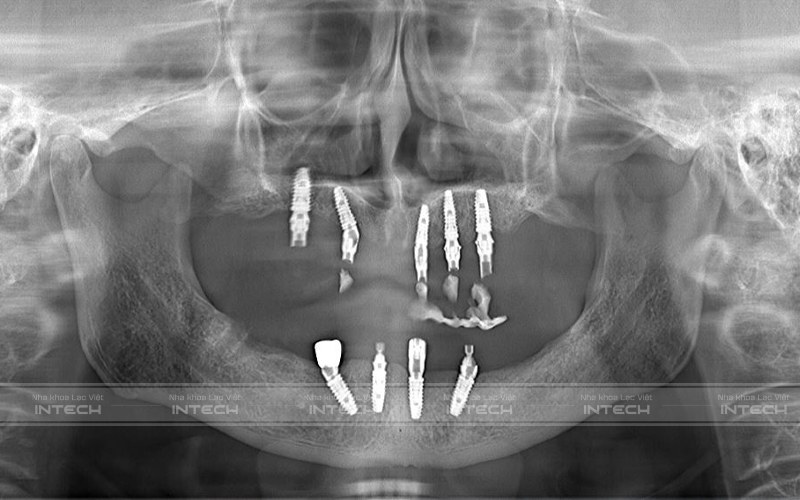

Qua thăm khám, chụp phim CT Conebeam và dựa trên các dữ liệu ban đầu, bác sĩ tại Nha khoa Lạc Việt Intech đánh giá chú Tĩnh gặp phải tình trạng cụ thể như sau:

• Mất toàn bộ răng hàm trên và nhiều răng hàm dưới

• Các răng còn lại không còn sử dụng được

• Cầu răng sứ hỏng, viêm chân răng

• Mất thẩm mỹ khuôn mặt, mất khả năng ăn nhai

Hình ảnh phim chụp sau cấy ghép implant của chú Tĩnh (Ảnh: Nha khoa Lạc Việt Intech)